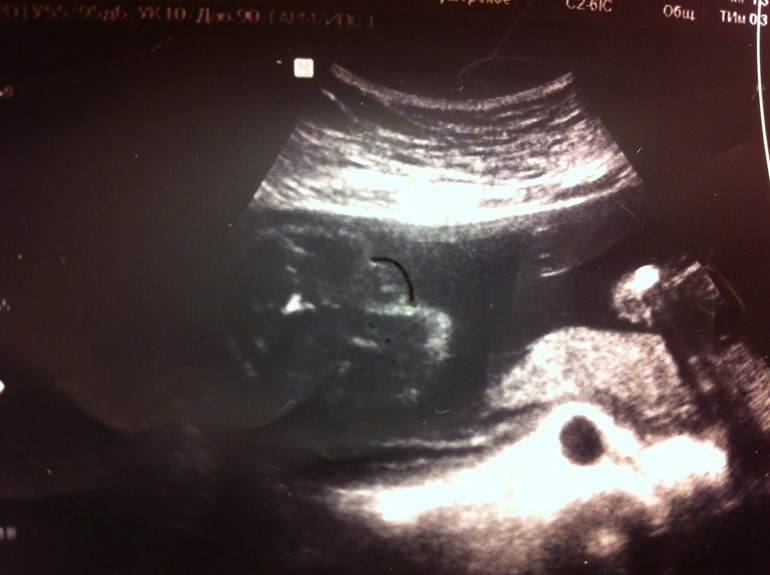

Может, кто по фото может все-таки что-то сказать? Первое фото - 24 неделя, где увидели девочку. 2 и 3 фото - 25 неделя, где увидели мальчика (врач маркером яички обвела). Пениса не видно, говорит, что это яички такие большие, половые губы такими не бывают... И тогда, и тогда говорят "100%". Ну смешно уже...

И тут мальчик: